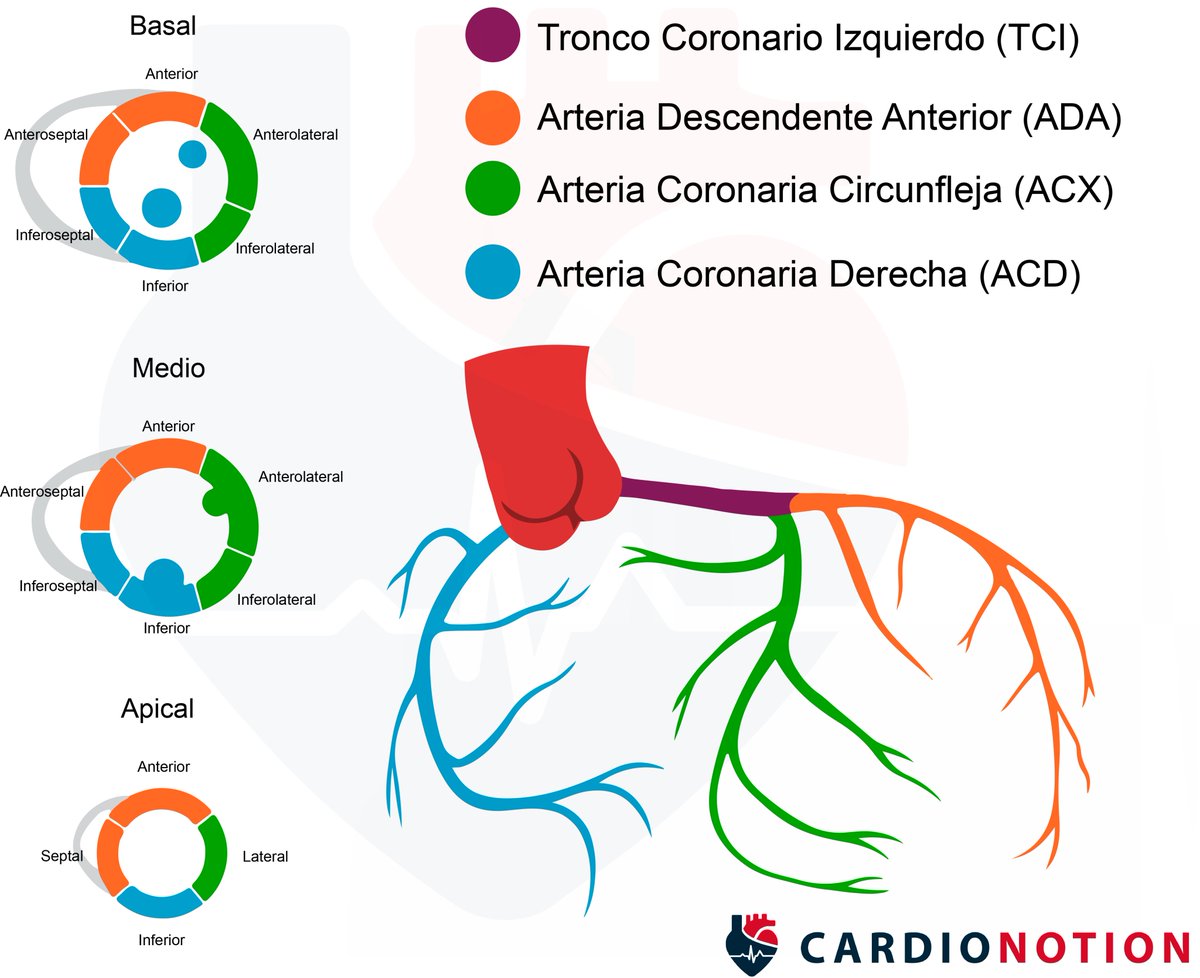

🫀Esquema simplificado de los segmentos cardíacos y su vascularización coronaria correspondiente 👇 #CardioNotion #CardioEd #MedEd #POCUS #Echofirst #ENARM #MIR #Cardiologia #echo

🫀Esquema simplificado de los segmentos cardíacos y su vascularización coronaria correspondiente 👇 #CardioNotion #CardioEd #MedEd #POCUS #Echofirst #ENARM #MIR #Cardiologia #echo